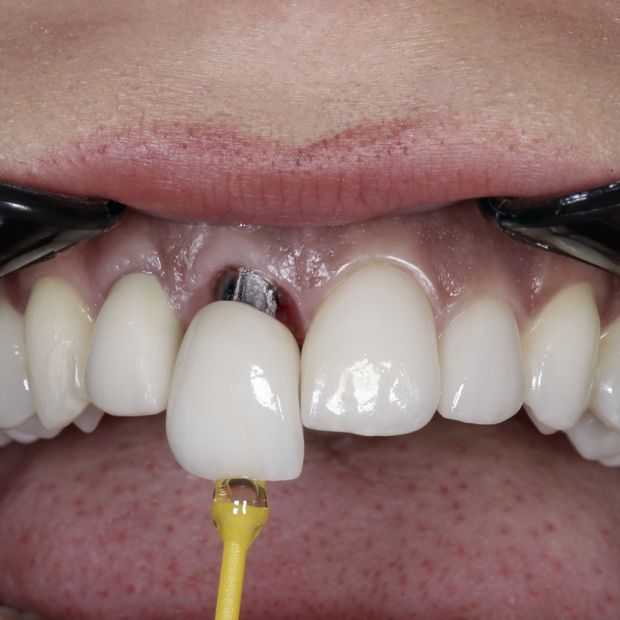

Implant Crown

You have probably met someone with Dental implants and didn’t even know it. Completely natural looking, tooth Implants have saved thousands of beautiful smiles. They have proven to be one of the most revolutionary advances in modern dentistry.